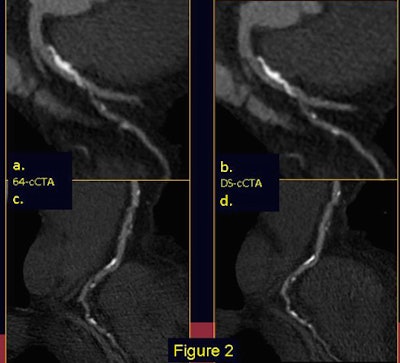

![]() |

| Electrocardiogram-gated 64-slice CT (a-c) and dual-source CT (b-d) in a patient with an extensive calcified plaque of the anterior descending artery (a-b) and multiple atherosclerotic irregularities of the right coronary artery (c-d). DSCT, with its sharper delineation of heavily calcified plaque borders, allows a substantial reduction of blooming artifacts, thereby limiting overestimation of plaque burden. |